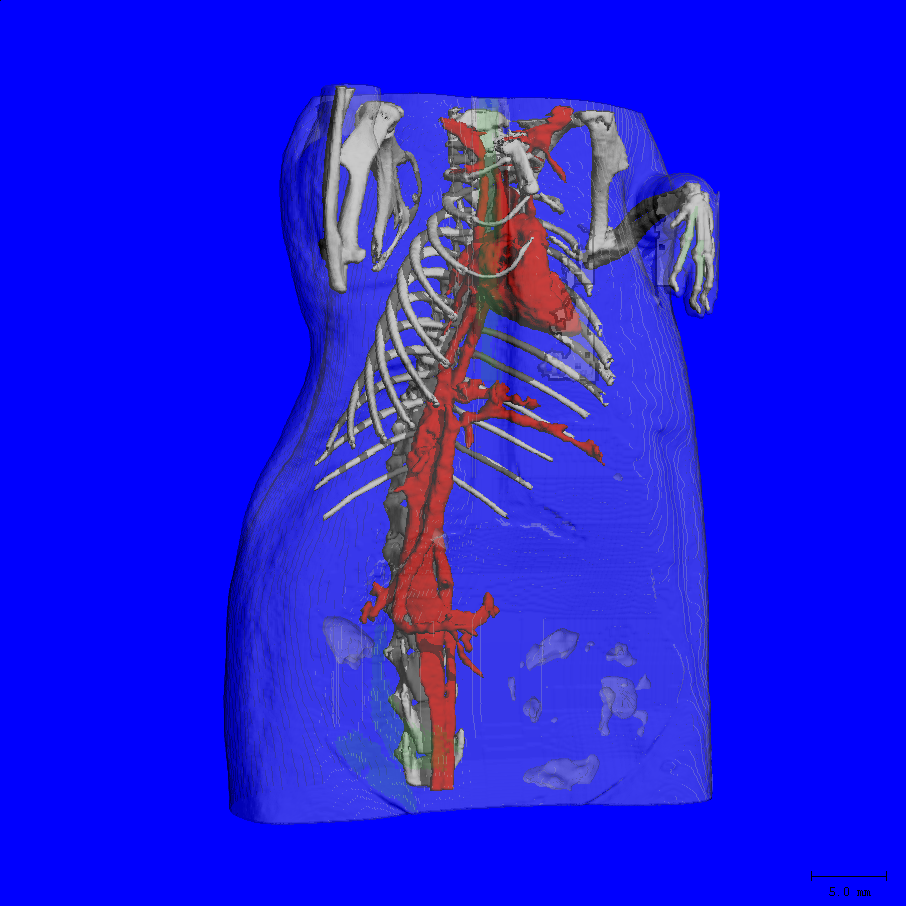

vivaCT80是SCANCO Medical AG 公司最新的活体产品,是vivaCT40和vivaCT75的升级产品,添加了触屏显示器、加热系统、呼吸麻醉接口,能够更好得监控动物的生存状态。vivaCT80的分辨率达到了3.9μm,样品仓也更大(90x500mm),配备大动物装置后可以扫描兔子头颅、四肢等体积较大的动物。研究对象通常为小鼠、大鼠或兔等活体小动物,麻醉或固定后扫描。可实现对组织、器官、生理功能代谢的纵向研究。

大动物装置